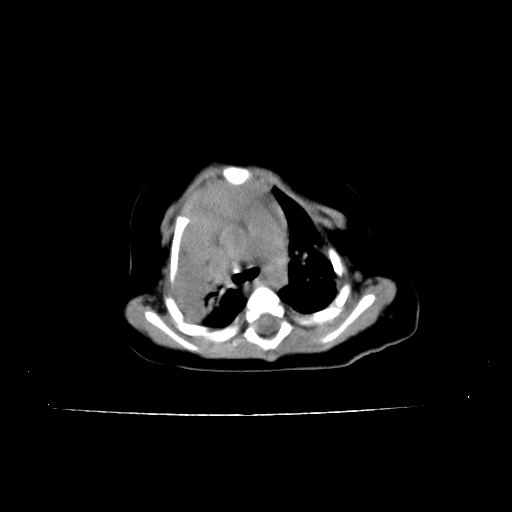

以下是引用影像之路在2009-5-8 15:46:00的发言:[br]1)胸廓畸形。2)考虑两肺感染性病变,并右肺上中叶肺不张;建议抗炎治疗后复查。3)胸腺肥大。4)前上中纵隔占位性病变待排;建议追踪复查。

以下是引用余辉在2009-5-8 8:44:00的发言:[br]鸡胸,胸腺肥大,双肺感染性病变,结合病史支原体肺炎可能性大